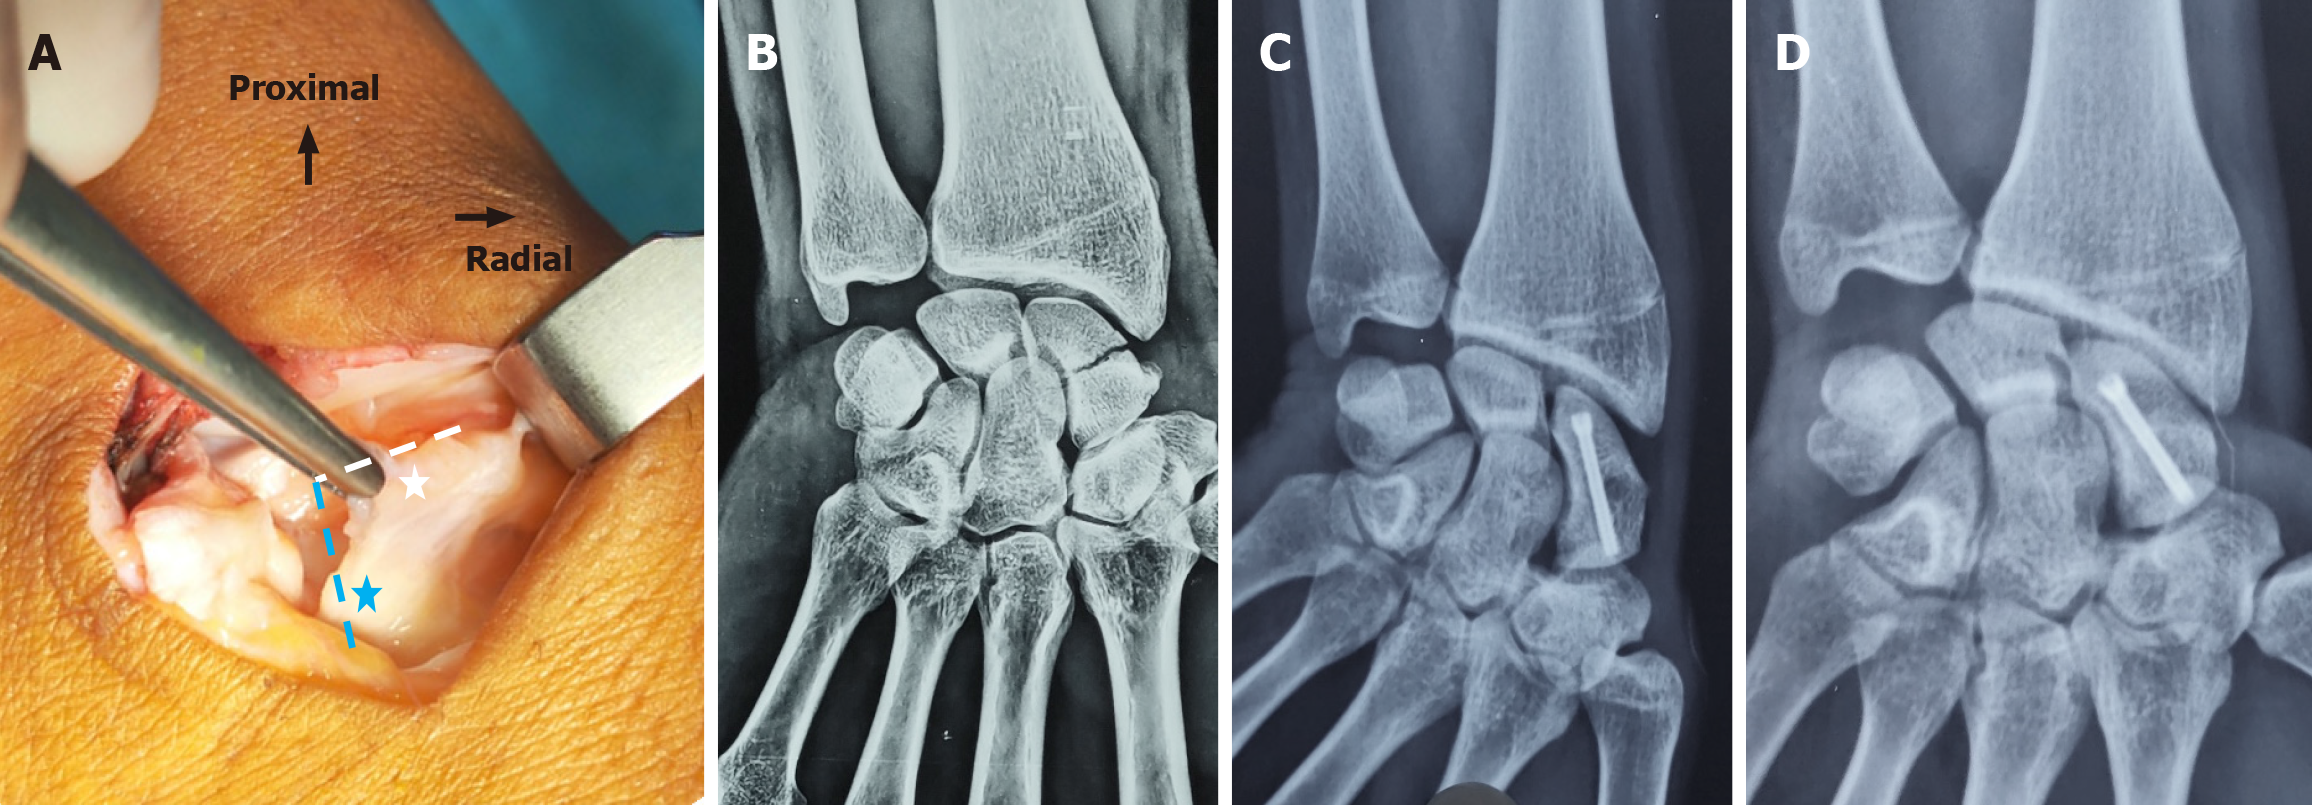

Figure 2 Radiographic evaluation of waist nonunion managed via the mini-dorsal approach.

A: Intraoperative clinical image demonstrating the inverted L-shaped capsulotomy used in the mini-dorsal approach. The transverse limb (white dashed line) is located at the radio-scaphoid interval, while the longitudinal limb (blue dashed line) lies ulnar to the scapholunate ligament interval; B: Preoperative anteroposterior radiograph showing a waist nonunion; C and D: Postoperative anteroposterior (C) and scaphoid-view (D) radiographs at seven months, showing complete healing.